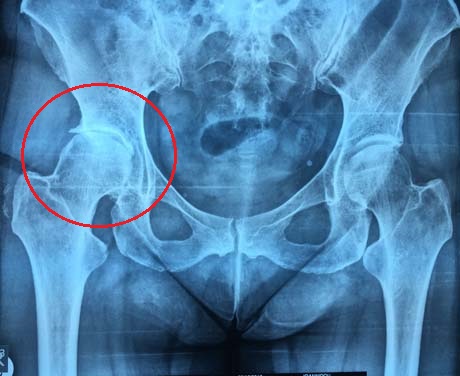

22-year-old patient with end-stage arthritis due to the LEG PERTHES CALVE disease which started when the patient was 12 years old. LEG PERTHES CALVE disease is one of the type of osteonecrosis of the hip that occurs in teens and its etiology has not been clearly elucidated to date.

Pre op X-ray of the hips reveals dysplasia and severe arthritis of the right hip